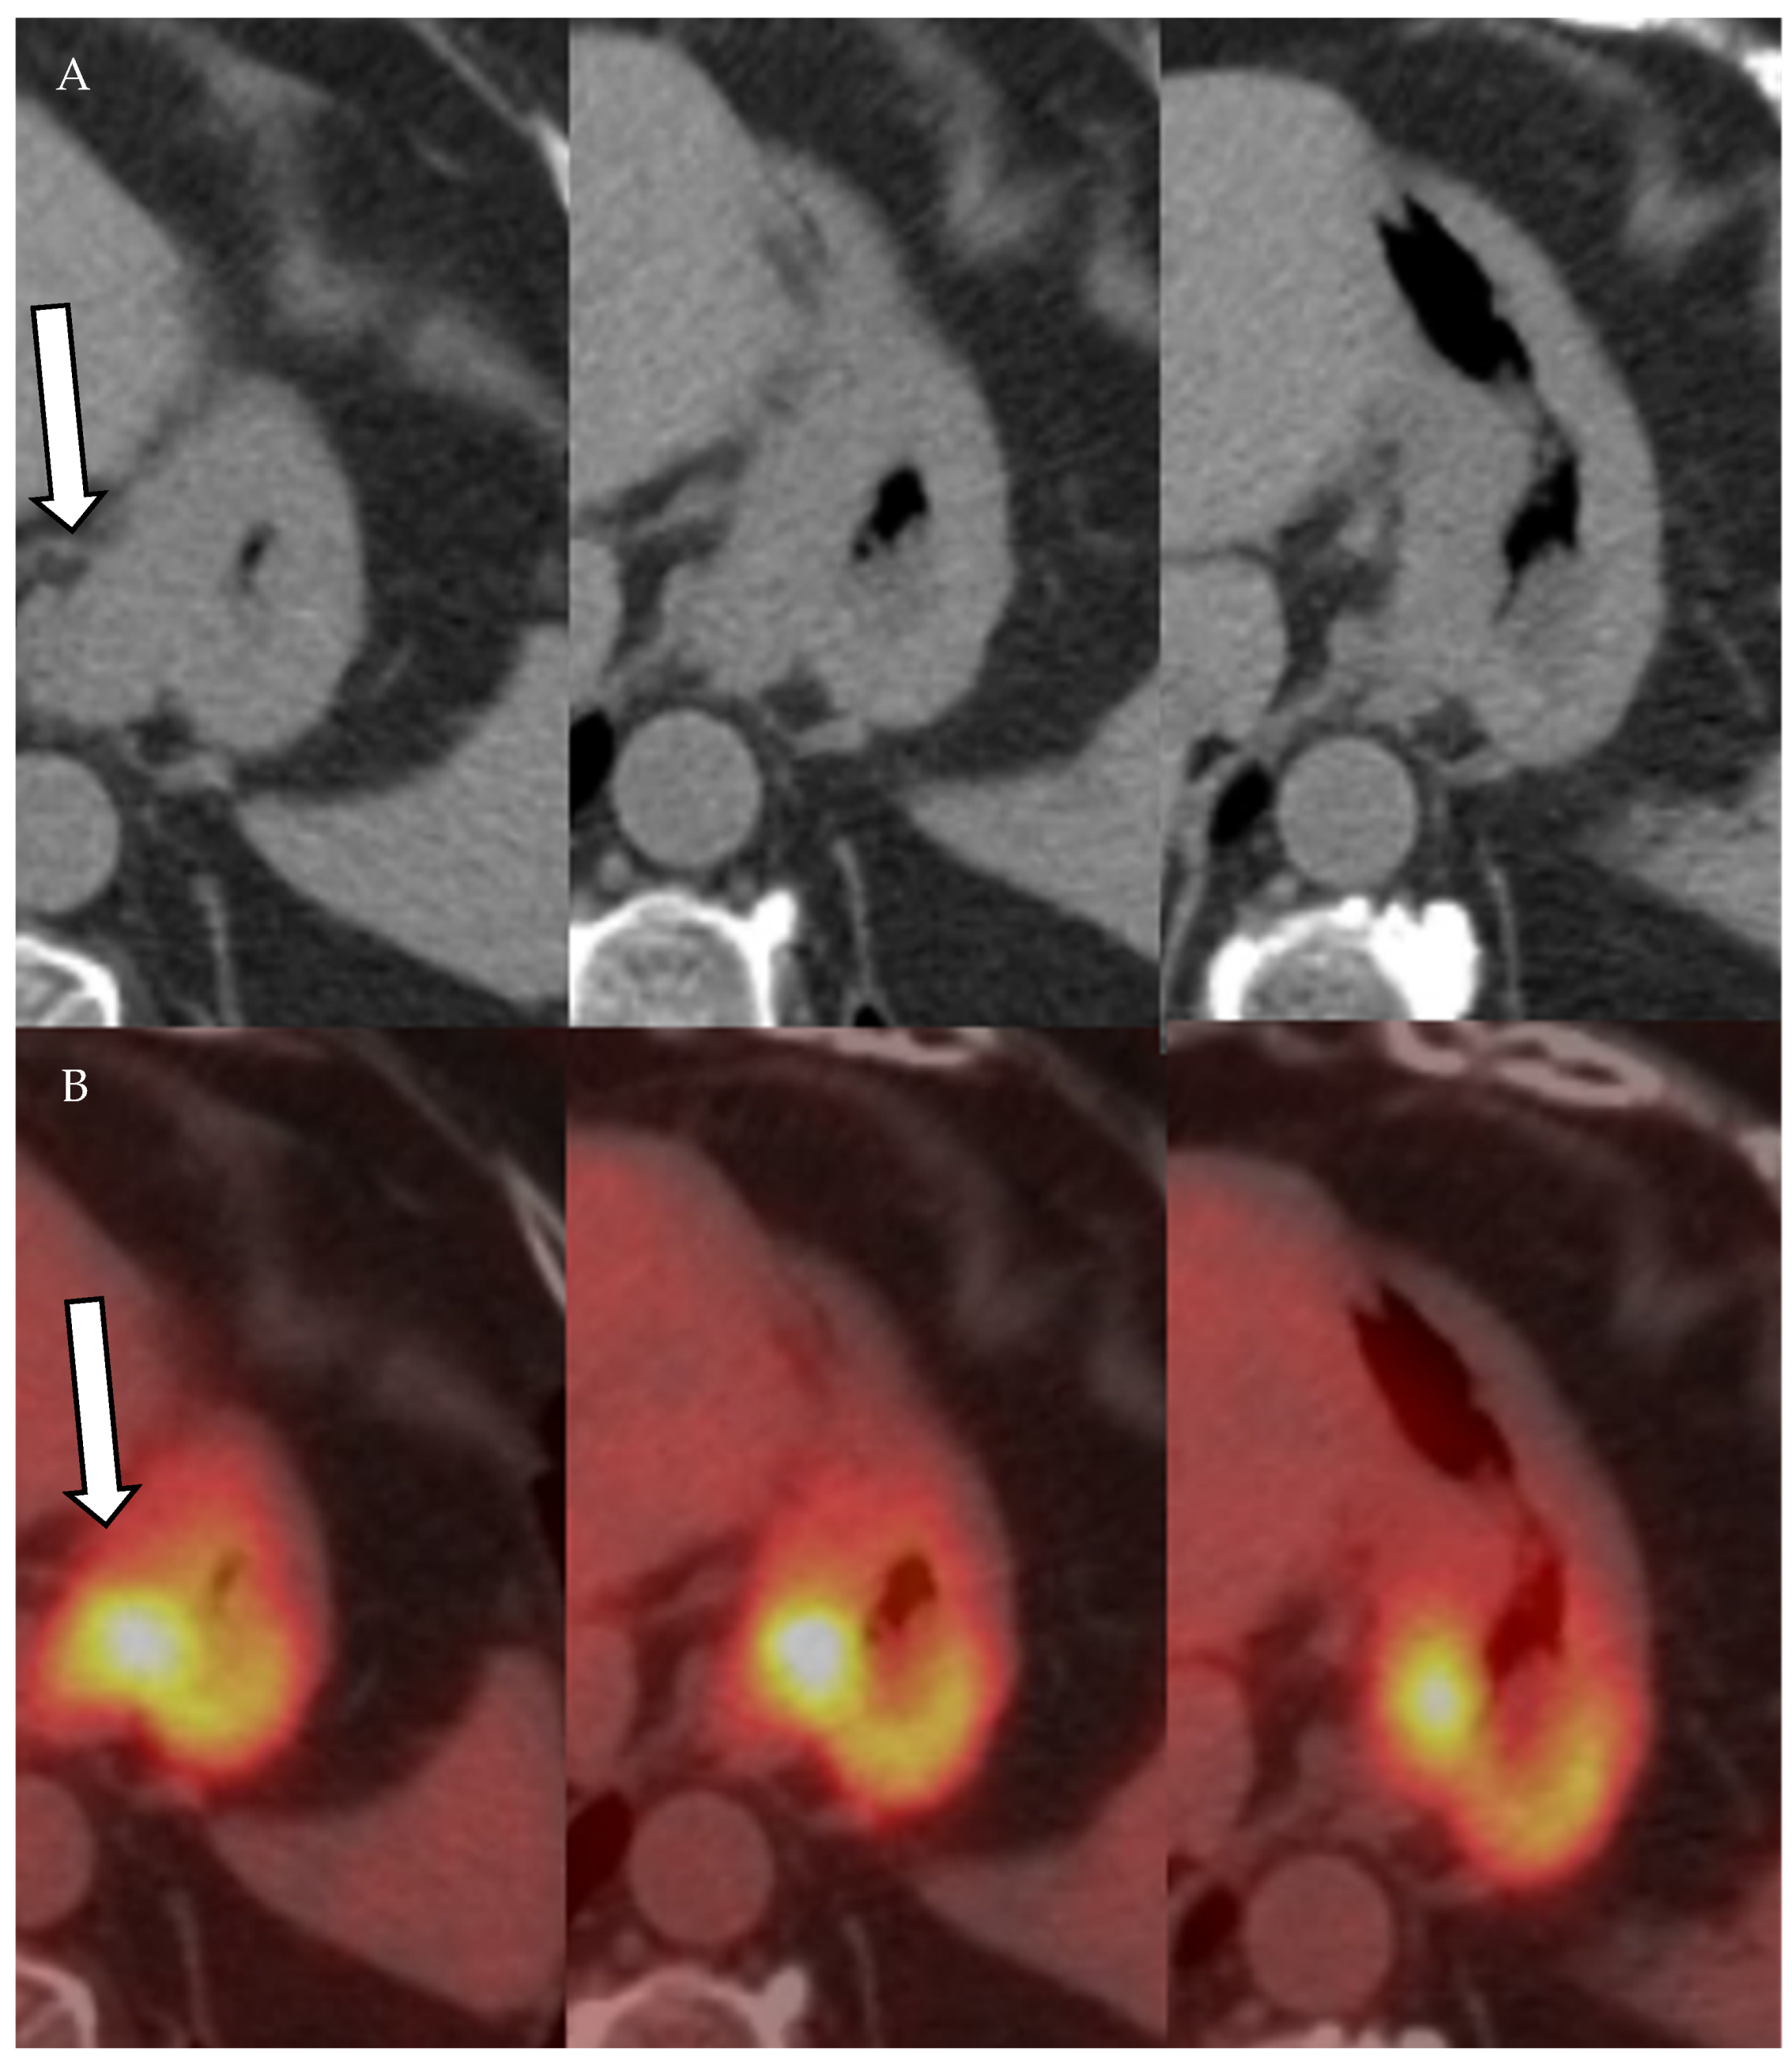

- Mittra, E.; Quon, A. Positron Emission Tomography/Computed Tomography: The Current Technology and Applications. Radiol. Clin. N. Am. 2009, 47, 147–160. [Google Scholar] [CrossRef]

- Vallabhajosula, S. 18F-Labeled Positron Emission Tomographic Radiopharmaceuticals in Oncology: An Overview of Radiochemistry and Mechanisms of Tumor Localization. Semin. Nucl. Med. 2007, 37, 400–419. [Google Scholar] [CrossRef] [PubMed]

- Liu, B.; Gao, S.; Li, S. A Comprehensive Comparison of CT, MRI, Positron Emission Tomography or Positron Emission Tomogra-phy/CT, and Diffusion Weighted Imaging-MRI for Detecting the Lymph Nodes Metastases in Patients with Cervical Cancer: A Me-ta-Analysis Based on 67 Studies. Gynecol. Obstet. Investig. 2017, 82, 209–222. [Google Scholar] [CrossRef] [PubMed]

- Choi, H.J.; Ju, W.; Myung, S.-K.; Kim, Y. Diagnostic performance of computer tomography, magnetic resonance imaging, and positron emission tomography or positron emission tomography/computer tomography for detection of metastatic lymph nodes in patients with cervical cancer: Meta-analysis. Cancer Sci. 2010, 101, 1471–1479. [Google Scholar] [CrossRef]

- Riegger, C.; Koeninger, A.; Hartung, V.; Otterbach, F.; Kimmig, R.; Forsting, M.; Bockisch, A.; Antoch, G.; Heusner, T.A. Comparison of the Diagnostic Value of FDG-PET/CT and Axillary Ultrasound for the Detection of Lymph Node Metastases in Breast Cancer Patients. Acta Radiol. 2012, 53, 1092–1098. [Google Scholar] [CrossRef] [PubMed]

- Cochet, A.; Dygai-Cochet, I.; Riedinger, J.-M.; Humbert, O.; Berriolo-Riedinger, A.; Toubeau, M.; Guiu, S.; Coutant, C.; Coudert, B.; Fumoleau, P.; et al. 18F-FDG PET/CT provides powerful prognostic stratification in the primary staging of large breast cancer when compared with conventional explorations. Eur. J. Nucl. Med. Mol. Imaging 2014, 41, 428–437. [Google Scholar] [CrossRef]